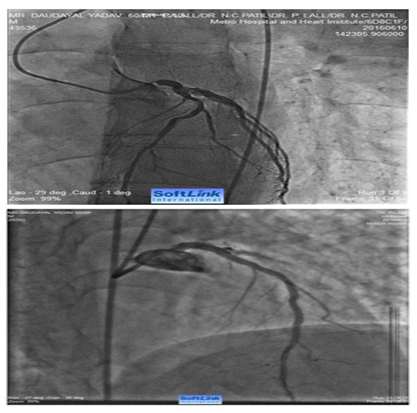

Figure 1 A 78 years old male with Class IV angina and LV ejection fraction of 0.3. Cranially angulated AP view shows 95% stenosis of ostial left main coronary artery (LMCA). Fluoroscopy showed extensive calcification involving LMCA, LAD and LCX. Corresponding image on the right side shows fully opened-up LMCA after ‘rota-stenting’ with a 1.5 mm burr and deployment of a drug eluting stent from LMCA to LAD.

Figure 2 A 60 years old male with recent anterior wall MI and LV ejection fraction of 0.35 with Class III exertional angina. Cranially angulated LAO view shows 95% stenosis of ostial left main coronary artery (LMCA). The ostial LMCA lesion was pulverized with a 1.5 mm RA burr (Boston Scientific International S.A., France) over a 0.009” RotaWire (Boston Scientific International S.A., France). Corresponding image on the right side shows fully opened-up LMCA.